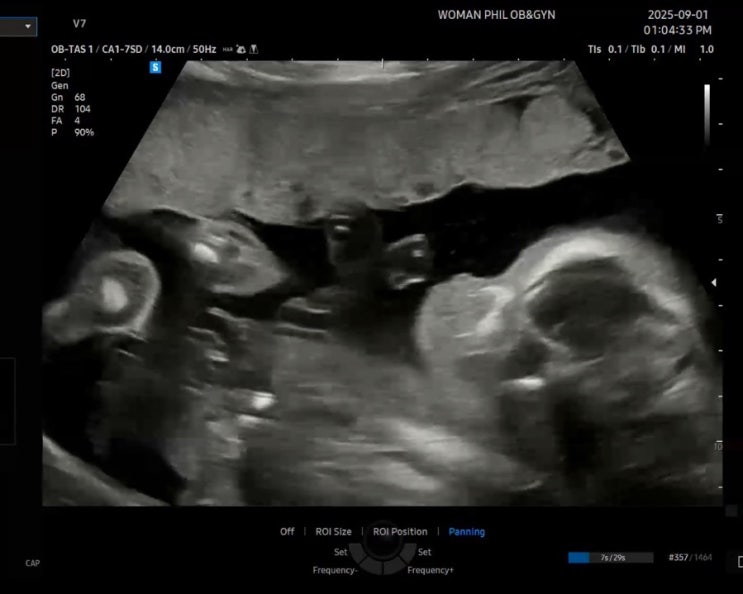

2025년 9월 임산부의 한 주 면접도 보고 감기도 걸린 일주일. 소소했던 일상 적어볼께요~~!! 9월 1일 월요...